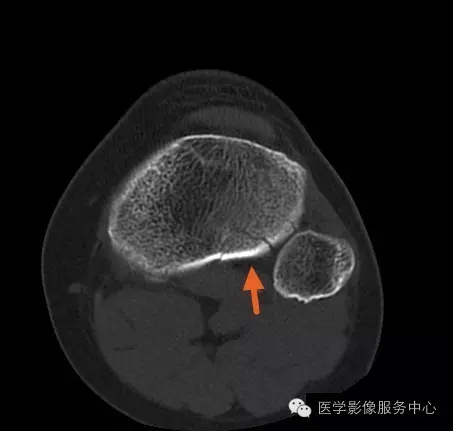

患者膝关节ct片显示骨关节受损

ct图像